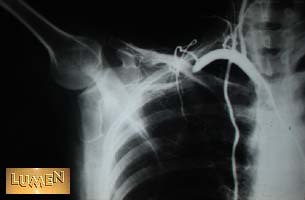

16. What muscles might compress the artery?

Anterior and middle scalenes.